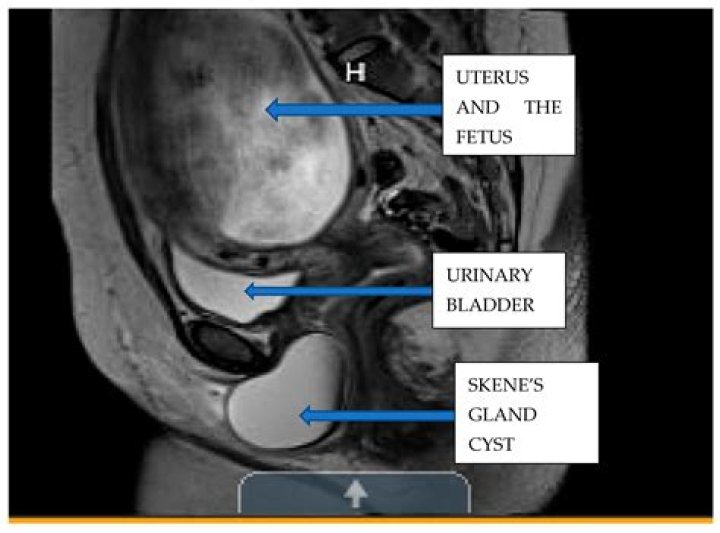

Skene glands (periurethral or paraurethral glands) are located adjacent to the distal urethra. Skene duct cysts form if the duct is obstructed, usually because the gland is infected. They occur mainly in adults. Cysts may become infected, leading to recurrent urinary tract infections (UTIs) and abscesses.

Periurethral Cystic Lesions. Periurethral cystic lesions include Gartner duct cyst, Bartholin gland cyst, Skene duct cyst, müllerian cyst, epidermal inclusion cyst, perineal-vulvovaginal endometriomas, and injected collagen.